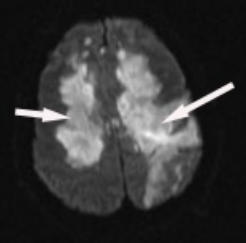

Patients with progressive obtundation can be challenging to evaluate and treat because of the breadth of disease entities that lead to nonfocal encephalopathy. In this patient, his course, the MRI findings, and findings in the cerebrospinal fluid (CSF) suggest the diagnosis of acute disseminated encephalomyelitis (ADEM). Specifically, ADEM is a postinfectious autoimmune encephalopathy that causes demyelination of the white matter with typical sparing of the cortical gray matter (Figure 2).

Axial diffusion-weighted MRI image. The findings show areas of patchy and confluent increased signal intensity with sparing of the cortex. There is also evidence of a subcortical hemorrhage in the left hemisphere (right side on screen) with increased signal intensity in the hemorrhage and cortical increased signal intensity, which likely represents perihematomal edema.

The arrow on the right shows the border of the white matter and gray matter. On this fluid-attenuated inversion recovery (T2-weighted) MRI image, the bright signal intensity is evidence of demyelination. Notice how on the left side of the image (right side of the brain), the demyelination respects the border between the cortex and white matter. On the other side (right arrow), the cortex is involved, which represents edema around an area of hemorrhage, which is also a hallmark of acute disseminated encephalomyelitis.